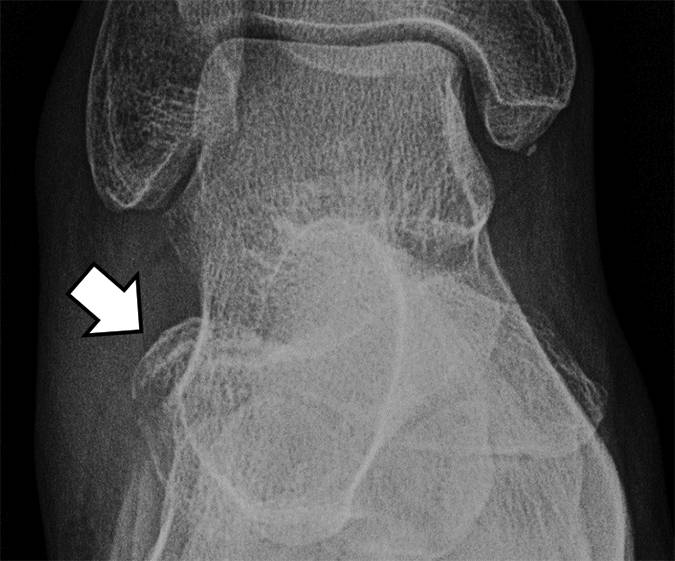

图9A-32岁的女性网球运动员,有背外侧瘀伤在脚。A,踝关节X线片显示移位与邻近软组织肿胀骨(箭头)的骨片即伸趾短肌的附着撕脱的特点。

图 9B-32岁的女网球运动员,她倒了她的脚和背外侧挫伤脚。B,足部X线片显示骨(箭头)的骨片位于背部和前跟骨体的外侧区。